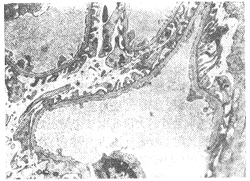

發病機制

細胞圖至於腎病產生高脂血症的機制尚不十分明確,但血脂過高乃繼發於蛋白代謝異常。尿蛋白大量喪失時,由於肝臟合成白蛋白增加,合成脂蛋白亦同時增加,成為高脂血症的原因此外,脂蛋白脂酶活力下降使脂質清除力降低亦為部分原因。